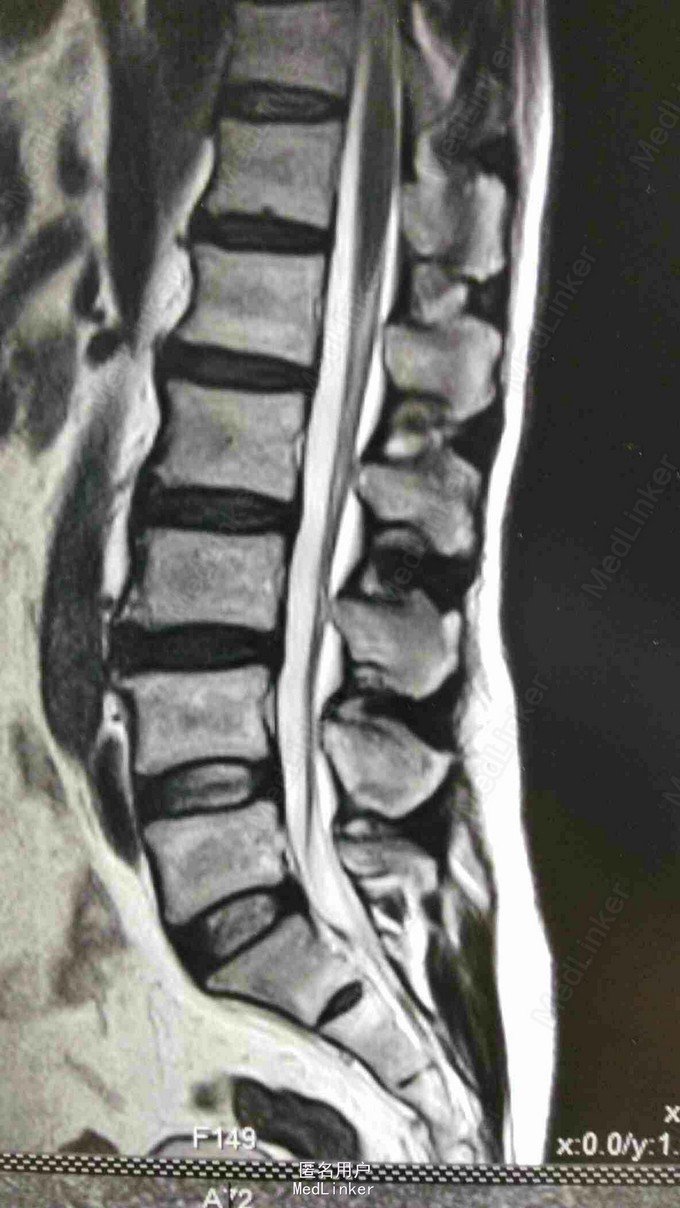

患者,男,59岁。20天前,患者无明显诱因出现右腿麻木,时有头晕、头痛、恶心等症状,亦未做过任何治疗,经休息后上述症状可缓解;在此期间,右下肢麻木逐渐加重,自觉行走无力。

脊柱序列如常,生理曲度存在,未见后凸及侧弯畸形。颈椎前屈、后伸、侧屈及旋转功能无明显受限,颈3-7椎间隙及棘突旁压痛。腰椎棘突及椎旁压痛,右小腿内侧皮肤感觉较左侧减退。

第一诊断:脊髓型颈椎病; 第二诊断:腰椎间盘突出症。 治疗:颈椎棘突间电针刺激每日一次,并针对颈腰椎进行按摩、熏蒸。 中药口服:半夏(清半夏)9g,生白术12g,天麻9g,柴胡12g,三棱9g,莪术9g,党参12g,黄芪15g,炒山药15g,陈皮6g,茯苓12g,生甘草6g。